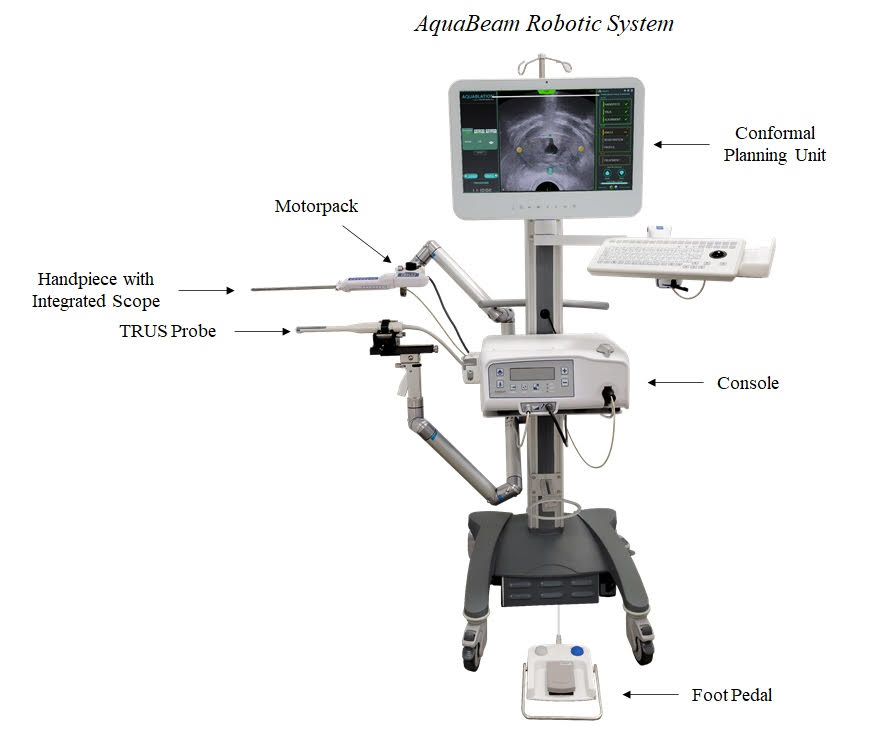

We are a surgical robotics company focused on advancing patient care by developing transformative solutions in urology. We develop, manufacture and sell the AquaBeam Robotic System, an advanced, image-guided, surgical robotic system for use in minimally invasive urologic surgery, with an initial focus on treating benign prostatic hyperplasia, or BPH. BPH is the most common prostate disease and impacts approximately 40 million men in the United States. The AquaBeam Robotic System employs a single-use disposable handpiece to deliver our proprietary Aquablation therapy, which combines real-time, multi-dimensional imaging, personalized treatment planning, automated robotics and heat-free waterjet ablation for targeted and rapid removal of prostate tissue. We designed our AquaBeam Robotic System to enable consistent and reproducible BPH surgery outcomes. We believe that Aquablation therapy represents a paradigm shift in the surgical treatment of BPH by addressing compromises associated with alternative surgical interventions. We designed Aquablation therapy to deliver effective, safe and durable outcomes for males suffering from lower urinary tract symptoms, or LUTS, due to BPH that are independent of prostate size and shape or surgeon experience. We have developed a significant and growing body of clinical evidence, which includes nine clinical studies and over 100 peer-reviewed publications, supporting the benefits and clinical advantages of Aquablation therapy. As of December 31, 2021, we had an install base of 130 AquaBeam Robotic Systems globally, including 78 in the United States.

We began developing our proprietary AquaBeam Robotic System in 2009 to address many of the shortcomings of alternative surgical interventions by delivering our Aquablation therapy, the first and only image-guided robotic therapy for the treatment of BPH. The AquaBeam Robotic System combines real-time image guidance, personalized treatment planning, automated robotic execution and heat-free waterjet ablation. We believe our Aquablation therapy addresses the compromise between safety and efficacy of alternative surgical interventions, providing the following unique combination of benefits:

•Outcomes independent of prostate size and shape and surgeon experience. We designed Aquablation therapy to deliver outcomes that are effective, safe and durable for males suffering from LUTS due to BPH across all prostate sizes and shapes. Our WATER, WATER II and OPEN WATER studies enrolled men with prostate sizes between 20 ml and 150 ml; however, in the commercial setting, we have successfully treated men with prostate sizes over 300 ml. Additionally, in the WATER and WATER II studies, 50% and 83% of men, respectively, had an obstructive median lobe, and the average prostate size in each study was 54 ml and 107 ml, respectively. Compared to other resective procedures, we believe Aquablation therapy is relatively simple to learn, enabled by the intuitive user interface of the conformal planning unit, or CPU, and automated robotic resection, and delivers outcomes that are independent of surgeon experience.

•Personalized treatment planning and improved decision-making. Aquablation therapy combines cystoscopic visualization, which uses a camera attached to a hollow tube, along with ultrasound imaging and advanced planning software to provide the surgeon with a multidimensional view of the treatment area and enable personalized treatment planning for the patient’s unique anatomy, improved decision-making and real-time monitoring during the procedure.

•Targeted and controlled resection with consistent resection times. Aquablation therapy utilizes automated robotic resection to remove prostate tissue using a precise, heat-free waterjet. These features enable targeted and controlled tissue removal with rapid resection times that are highly consistent across prostate sizes and shapes and surgeon experience.

•First and only image-guided, heat-free robotic therapy for BPH that addresses the compromise between safety and efficacy of alternative surgical interventions. We have developed the AquaBeam Robotic System, an advanced, image-guided, surgical robotic system for use in minimally invasive BPH surgery. The AquaBeam Robotic System delivers our Aquablation therapy, the first and only image-guided, heat-free robotic therapy for the treatment of BPH. Aquablation therapy combines real-time, multidimensional imaging, personalized treatment planning, automated robotics and heat-free waterjet ablation for targeted and rapid removal of prostate tissue. We believe that alternative surgical interventions for BPH have a number of shortcomings which require patients to compromise between safety and efficacy, either providing significant symptom relief but with a heightened risk of irreversible complications or a lower risk of complications but with significantly less symptom relief. We believe Aquablation therapy represents a paradigm shift in the surgical treatment of BPH by addressing this compromise.

•Compelling value proposition and benefits to hospitals, surgeons and patients. We designed our AquaBeam Robotic System to enable consistent and reproducible BPH surgery outcomes that are independent of surgeon experience and require minimal training. In addition, we believe the differentiated features of Aquablation therapy allow for improved predictability of outcomes and, as such, increase surgeon confidence in recommending surgical intervention to their patients. Given its ability to treat prostate sizes of all shapes and sizes, Aquablation therapy enables hospitals to consolidate the surgical treatment of BPH in a single therapy. We also believe that hospital administrators will be able to leverage the differentiation of Aquablation therapy as a marketing tool to attract skilled surgeons and patients to their hospital system. Furthermore, the AquaBeam Robotic System is highly mobile and compact, requiring no retrofitting of the operating room, and we believe is competitively priced compared to other robotic systems and capital equipment devices, both factors which we believe remove adoption hurdles for hospital customers and allow for a more streamlined hospital sales cycle. For patients, Aquablation therapy offers significant and durable symptom relief with an attractive safety profile. We believe these benefits will continue to support the adoption of Aquablation therapy by hospitals and surgeons.